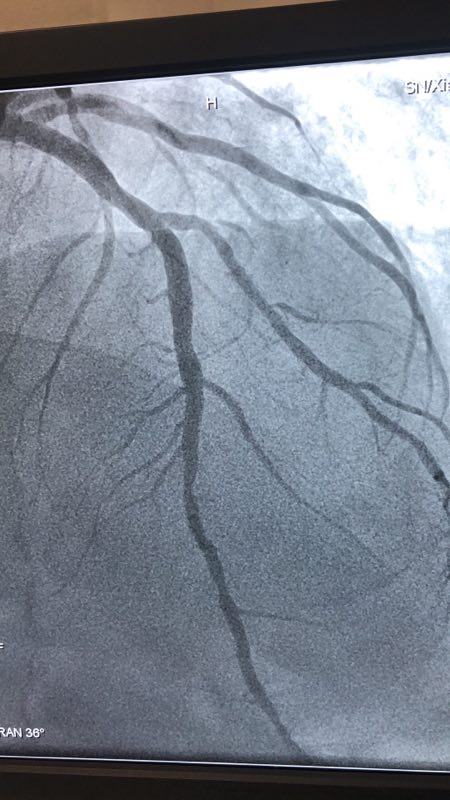

此例患者,男性,56岁,11年前因心绞痛在西京医院行冠状动脉造影检查后于D1对角支置入1枚支架治疗。术后患者口服“阿司匹林肠溶片、氯吡格雷、阿托伐他汀”等药物治疗1年后自行停药,并有长期大量吸烟史。2018年12月24日患者突发胸痛、胸闷,急来我院就诊。急诊行冠状动脉造影检查提示D1对角支原支架内再狭窄70%-90%。急救中心主任张誉洋副主任医师考虑到第一对角支管径较小,于原支架内再次置入支架引起再狭窄的风险极大,遂建议应用药物涂层球囊扩张术治疗D1对角支原支架内狭窄。与患者充分沟通后,于12月27日行冠脉药物涂层球囊PTCA术治疗,造影显示血管开通情况良好,术后患者症状明显改善。